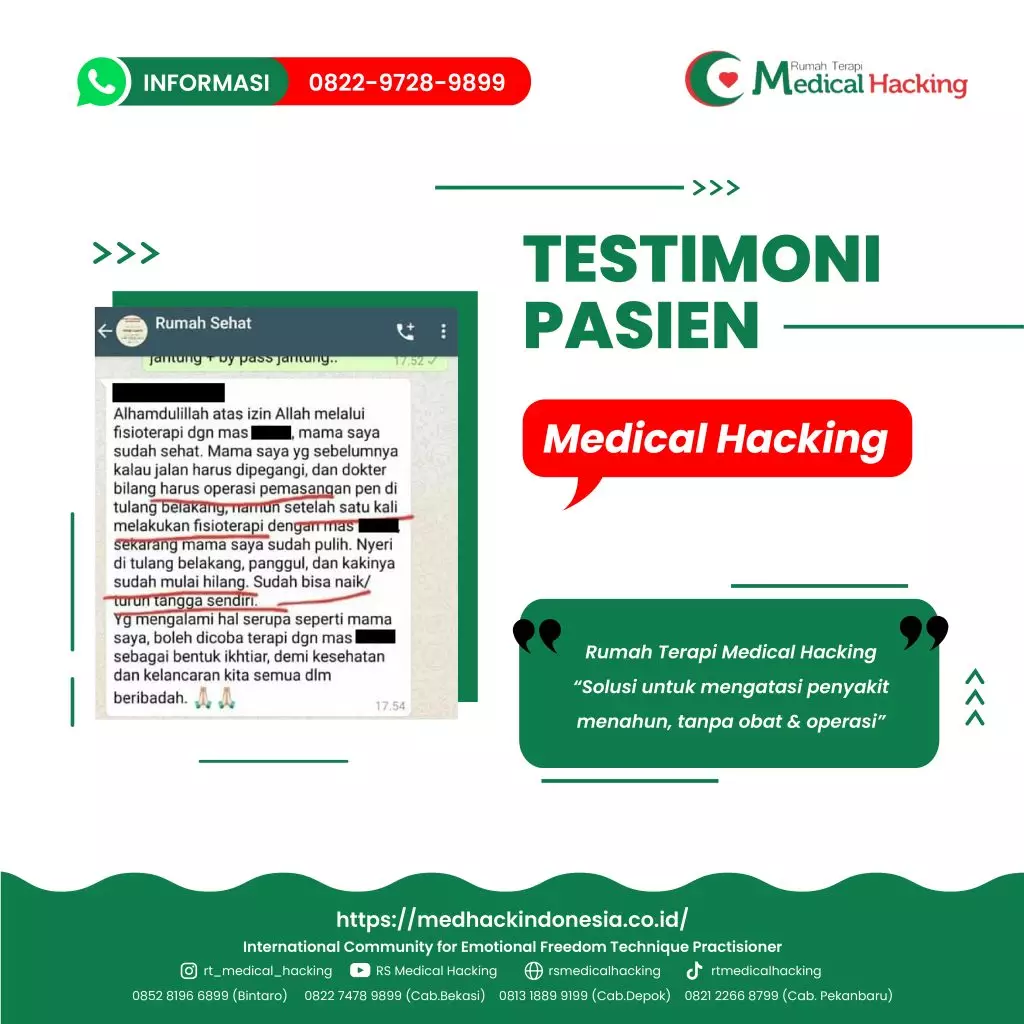

Rumah Terapi Medical Hacking merupakan tempat terapi yang dapat diandalkan untuk mengobati berbagai penyakit secara alami dan menyeluruh, salah satunya adalah radang sendi lutut. Medical Hacking telah dikenal luas sebagai penyedia terapi non-obat kimia yang sudah membantu banyak orang yang kini sudah dinyatakan pulih dari berbagai kondisi medis.

Dengan metode yang mengutamakan keseimbangan tubuh secara alami, Rumah Terapi Medical Hacking telah dipercaya mampu memberikan hasil terapi yang aman dan optimal tanpa efek samping dalam jangka panjang.